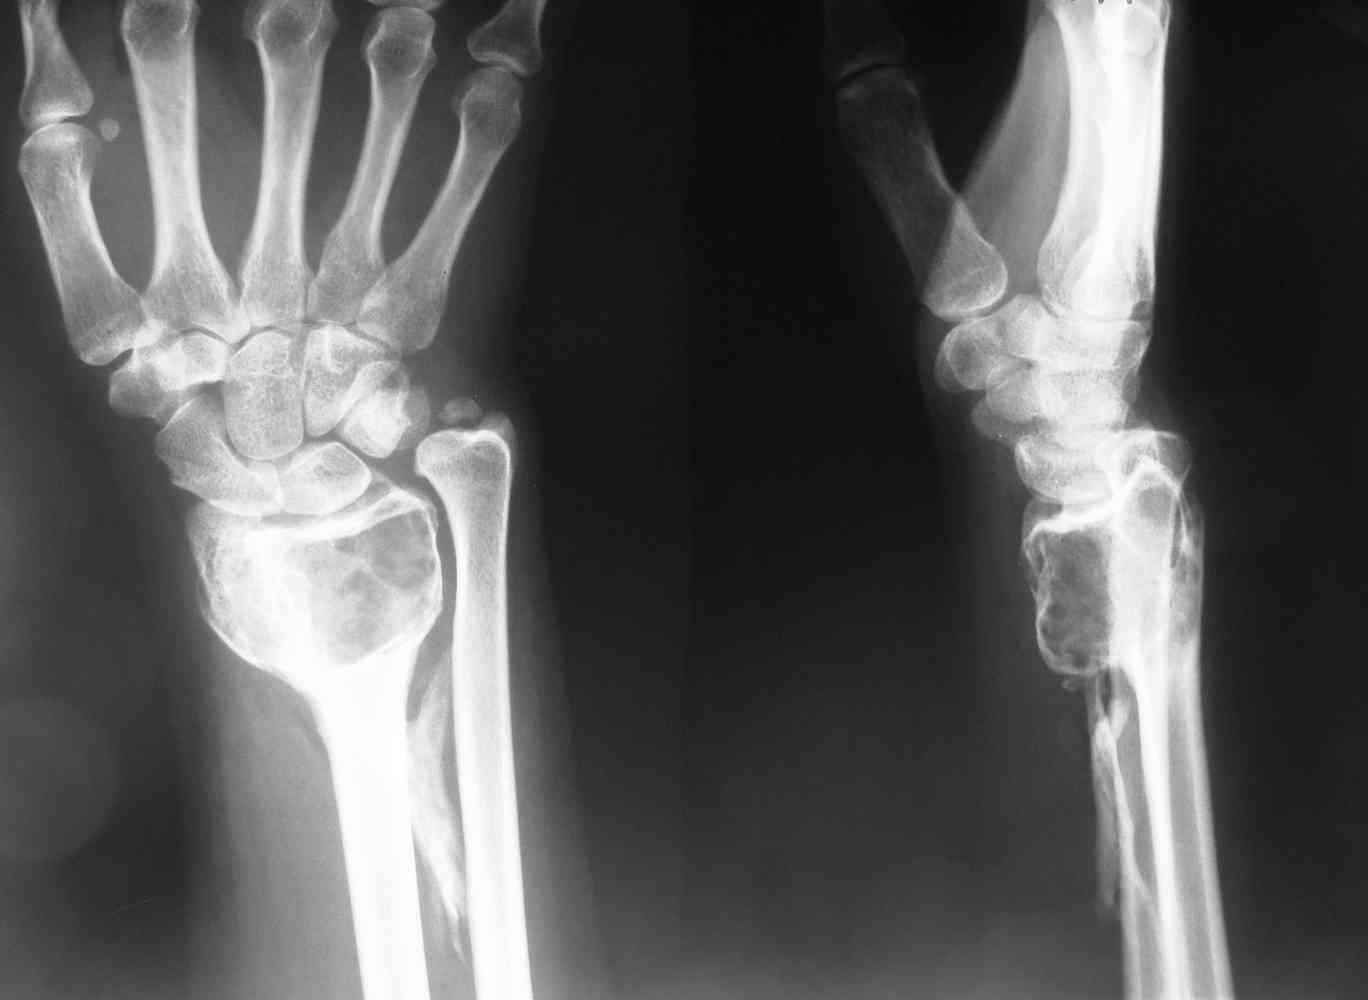

ОБК дистального эпифиза левой лучевой кости

Здравствуйте, уважаемые коллеги! На приём обратилась молодая женщина 28 лет с жалобами на наличие образования в области левого лучезапястного сустава.

Болевой синдром умеренный, "ночных" болей нет. Полтора года назад - патологический перелом дистального эпиметафмза левой лучевой кости. В Областном онкодиспансере выполнена открытая биопсия патологического очага.

Морфологическое заключение: остеобластокластома без признаков малигнизации.

Уважаемые коллеги! Что можно предпринять в данном случае с учётом максимального сохранения функции верхней конечности? Возможна ли в данном случае замена поражённого участка лучевой кости онкологическим протезом? Заранее благодарны за помощь!